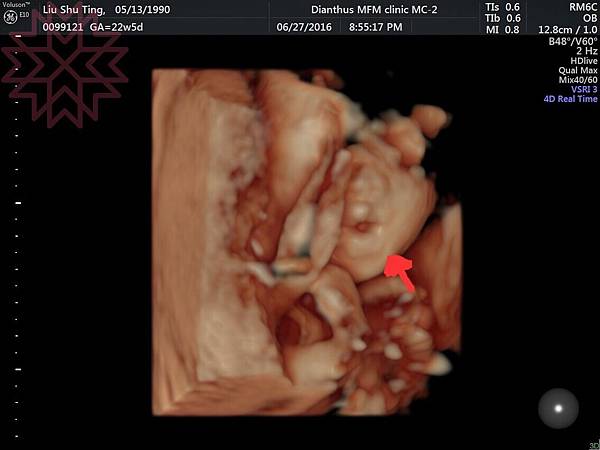

4D臉部照~剛好拍到葉黃素的裘莉式性感豐唇哈哈哈

超Q低~

就是這樣哈哈哈哈哈哈哈哈(不得不說小手好可愛)